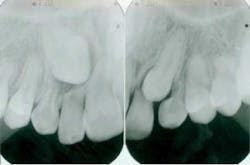

Top clinical articles

Top endodontics articles